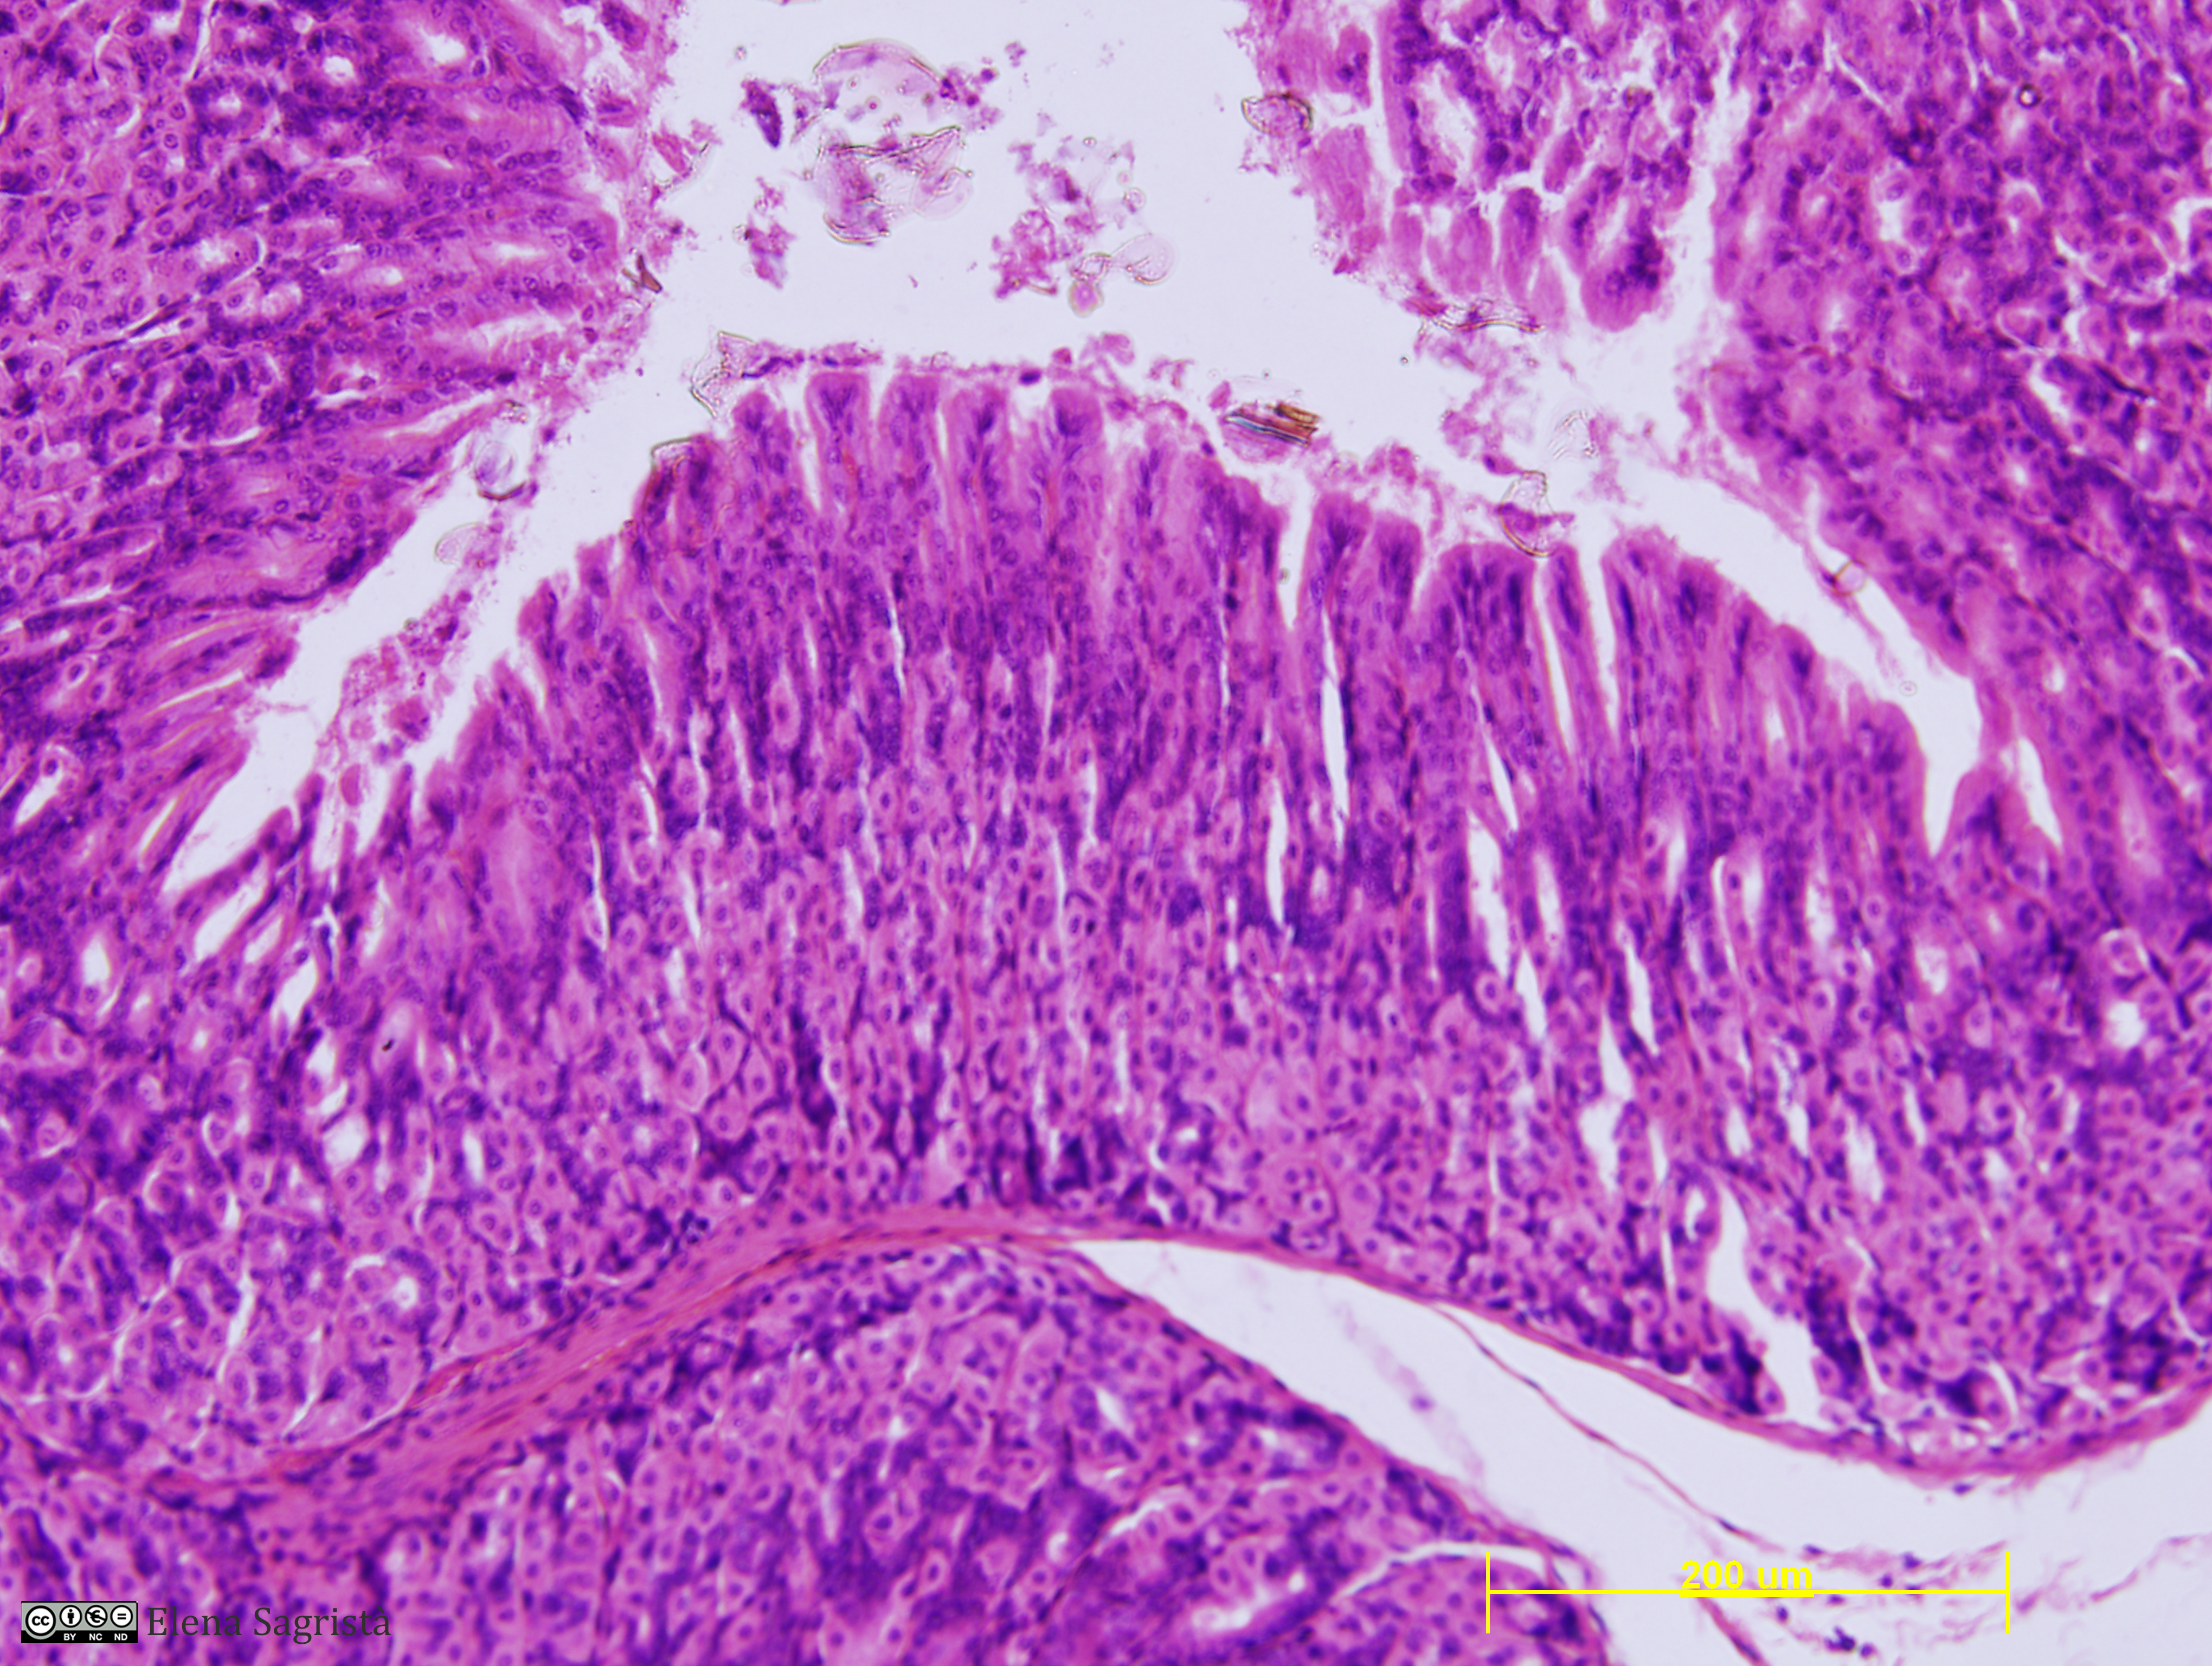

Histologia imatges: 16 Estòmac

Imatges de preparacions histològiques d'Estómac. Microscopia òptica.